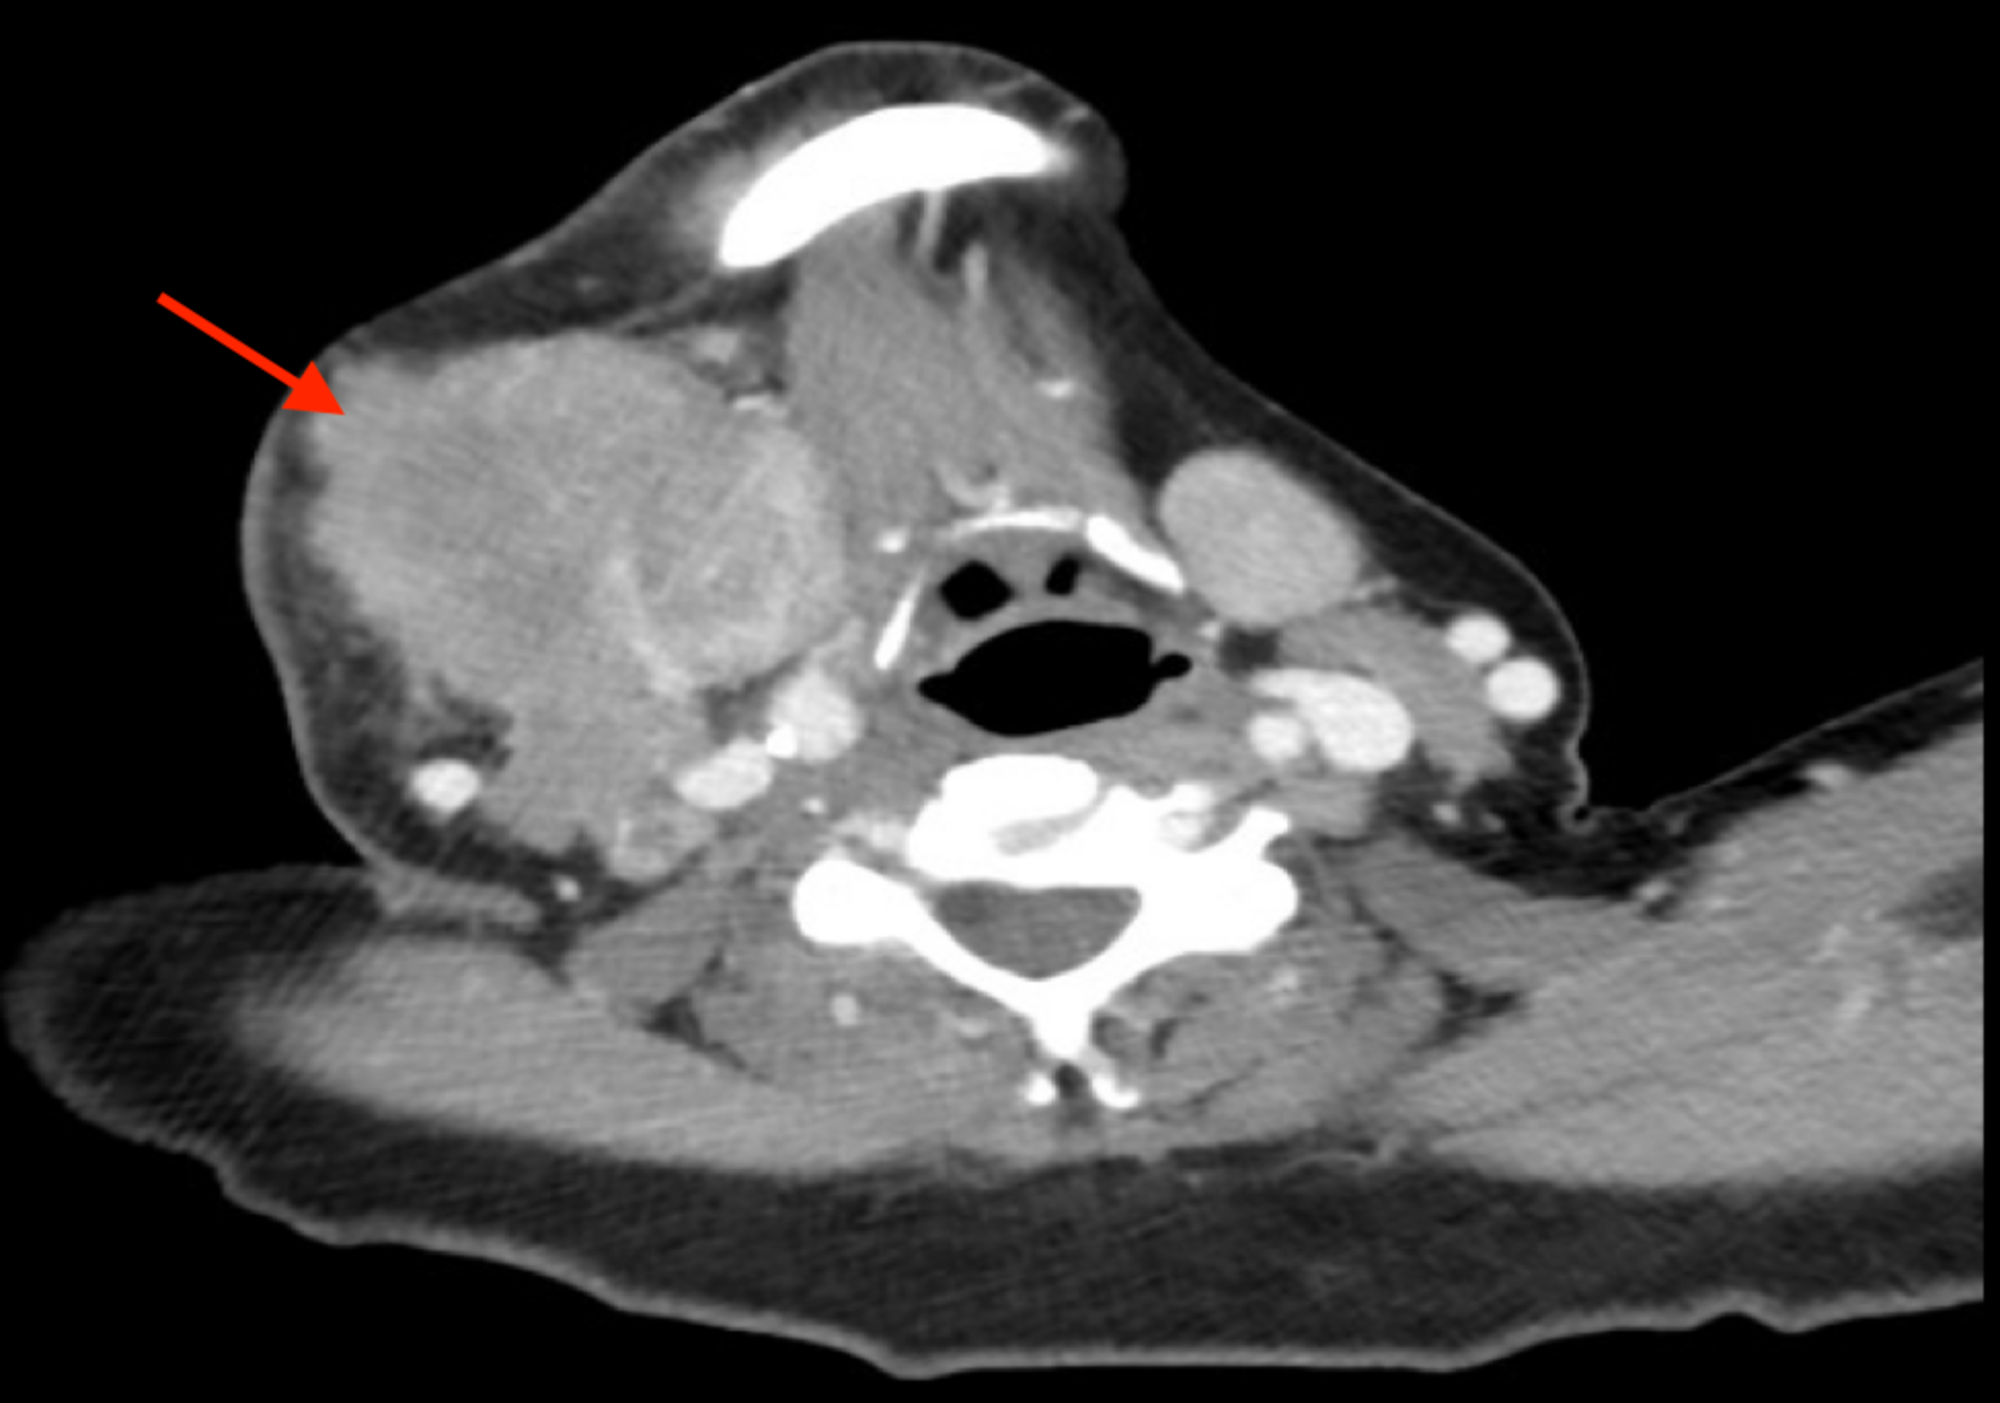

Cureus | An Unusual Case Of Alveolar Rhabdomyosarcoma Of The Neck In An

www.cureus.com

www.cureus.com

neck ct rhabdomyosarcoma alveolar patient unusual case adult figure scan enlarging mass region showing cureus

An Unusual Case Of Alveolar Rhabdomyosarcoma Of The Neck In An Adult

www.cureus.com

www.cureus.com

neck rhabdomyosarcoma alveolar patient submandibular enlarging mass right figure unusual case adult cureus